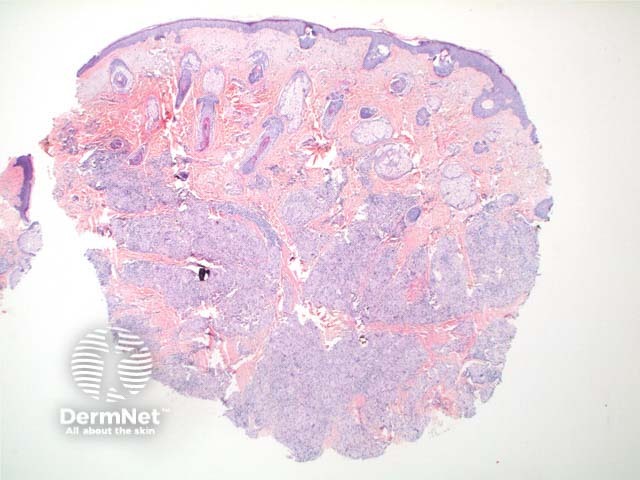

Scanning power view of sarcoidosis shows a granulomatous reaction pattern (Figure 1) characterised by multiple discrete predominantly epithelioid granulomas (Figures 2 and 3). Necrosis is uncommonly seen. The granulomas are typically ‘naked’ with few surrounding lymphocytes and a rim of mild dermal fibrosis.

Figure 1